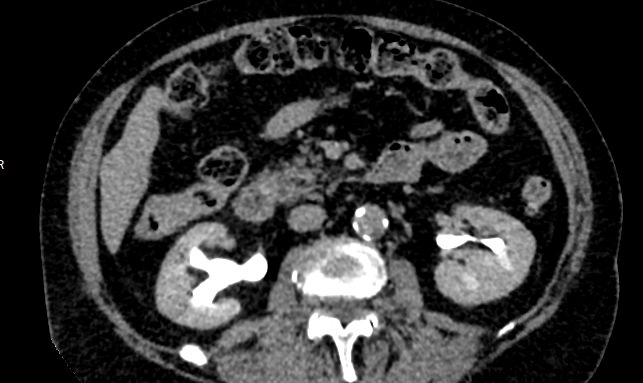

Мультиспиральная компьютерная томография почек и мочевыводящих путей  является высокоинформативным методом исследования, основанном на использовании воздействия рентгеновских лучей на органы и ткани человека. Методика предусматривает послойное сканирование области почек, мочевыводящих путей и получение снимков исследуемой области в мельчайших подробностях.

Для улучшения визуализации патологических очагов (различных кист или новообразований) в некоторых случаях дополнительно применяется контрастное усиление. Для этого пациенту внутривенно вводится йодсодержащее контрастное вещество, которое накапливается в патологически измененных участках и вызывает их яркое контрастирование на фоне здоровых тканей.

МСКТ почек и мочевыводящих путей с контрастированием позволяет выявить опухолевые образования на ранних стадиях, отличить доброкачественную опухоль от злокачественной, определить размеры опухоли, точную локализацию и степень распространения в окружающие ткани. Компьютерная томография почек с внутривенным болюсным контрастированием необходима для определения тактики лечения и объема оперативного вмешательства.